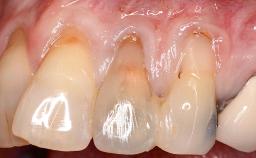

A 30-year-old woman was referred by her general dentist for evaluation of an esthetic complication related to previous implant treatment for congenitally missing maxillary lateral incisors. The patient’s chief complaint was the inadequate esthetic appearance of her smile. The case demonstrates the use of a combined approach to achieve optimal results. Two different flap designs - a tunnel technique and a coronally advanced flap - are employed based on the surgical objectives for the affected site.

Soft Tissue Anatomy Intact Defective

Soft Tissue Contour and Volume Slightly compromised